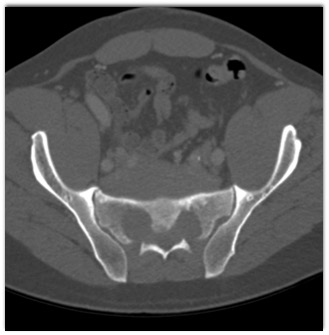

The best diagnosis in this case of a patient with back pain is?

extramedullary hematopoiesis

myeloma

lymphoma

Ewings sarcoma